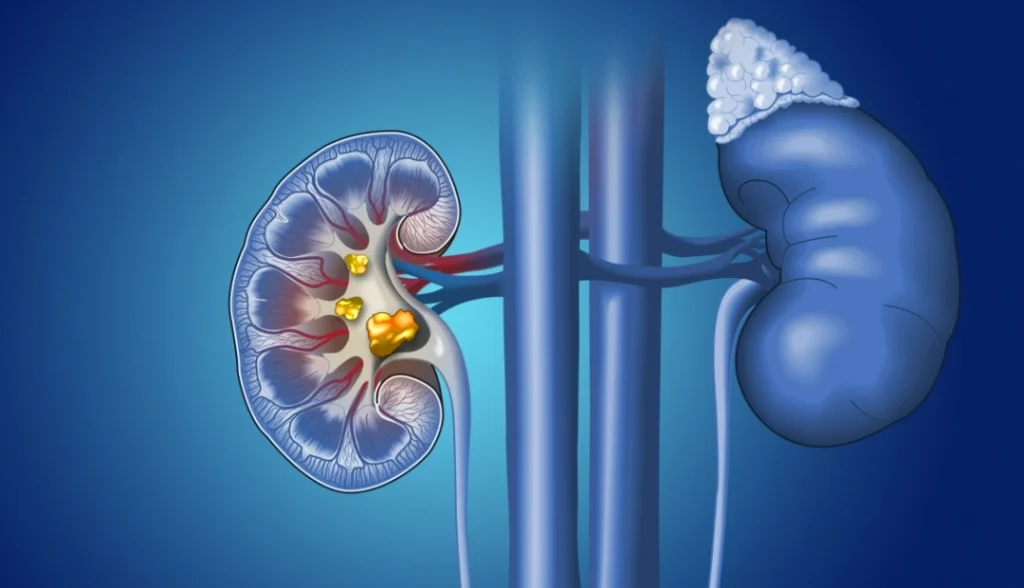

La litotrissia percutanea (PCNL per gli autori anglosassoni) rappresenta a tutt’oggi il trattamento di prima scelta per i calcoli renali superiori a 2 cm di diametro: viene eseguita attraverso un accesso percutaneo nel fianco che consente di accedere al rene. Questa procedura è nel più delle volte eseguita dall’Urologo o dall’Urologo coadiuvato dal Radiologo Interventista.

Viene creato un tramite nefrostomico percutaneo attraverso cui si introduce il nefroscopio. Quest’ultimo consente la visualizzazione diretta del calcolo e l’introduzione nella via escretrice di particolari sonde (ultrasuoni, laser). Queste consentono la frantumazione del calcolo renale.

Al termine della fase di litotrissia, i frammenti litiasici vengono asportati attraverso il nefroscopio con l’ausilio di pinze o basket.